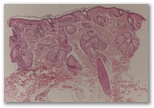

Paciente en tratamiento con amiodarona que consulta por un cuadro intolerancia luminica facial

Diagnostico